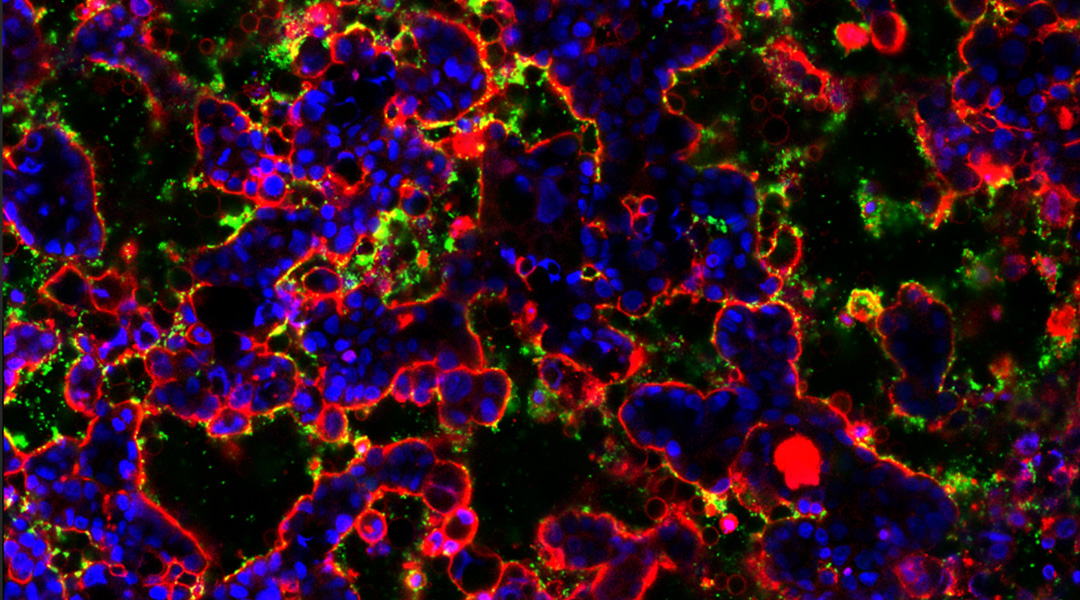

Cowpea virus immunotherapy prevents cancer metastases

Plant-based virus stimulates the body’s immune response to fight off established and budding cancer metastases.

Cowpea virus immunotherapy prevents cancer metastases

Plant-based virus stimulates the body’s immune response to fight off established and budding cancer metastases.